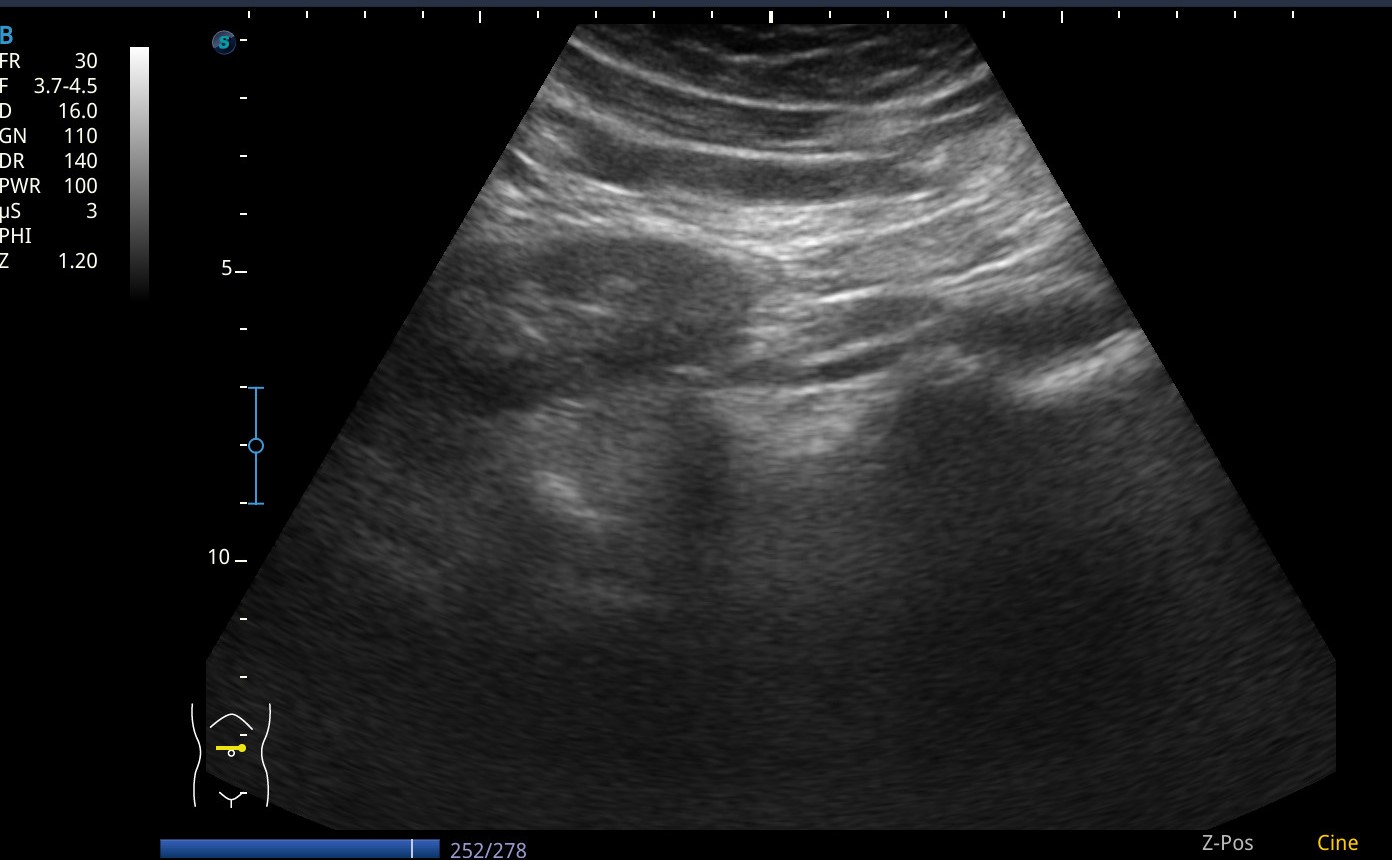

Se realiza ecografia a pie de cama que muestra como en el flanco derecho presenta silueta renal con un polo superior visible, sin poder definir el polo inferior, y la misma imagen en la silueta renal izquierda.

Asi mismo vemos a nivel de epigastrio bajo (zona umbilical), tejido sugestivo de parénquima renal que cruza por delante de grandes vasos, imagen compatible con un riñon en herradura.

En pelvis renal izquierda se aprecia una imagen hiperecogénica, sugestiva de microlitiasis.